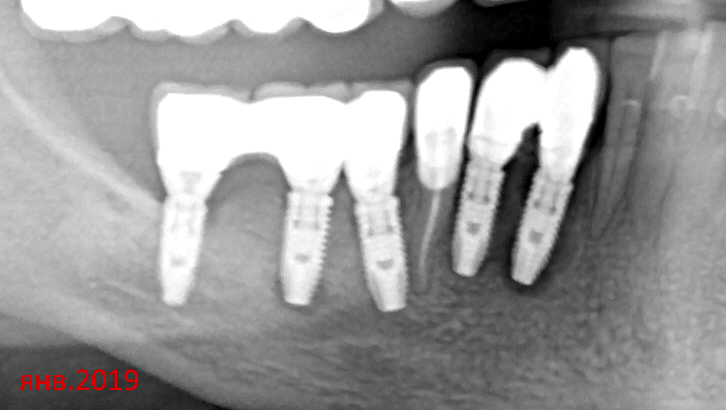

kramer Опубликовано 15 апреля, 2021 Поделиться Опубликовано 15 апреля, 2021 Пациентке летом 2018 г установили имплантаты, какие-то одномоментно, какие-то нет, не помнит. Коронки через 3 месяца, цементная фиксация. Вскоре после этого начались жалобы на боль, дискомфорт в области всех имплантатов, особенно 42 и 43. Лечащий врач контрольных снимков не делал, утверждал, что все в порядке. Обратилась к нам, на ОПТГ признаки резорбции кости в обл. имплантата 43 и апикально у импл. 46. Посоветовал ей подойти с этим снимком к своему врачу. Далее с ее слов врач демонтировал коронки 42-43, что-то там чистил (цемент?), зафиксировал обратно (причем как видно, одна из коронок не досела). Новый снимок от 15.04.21 - как-будто ничего и не было. Жалоб сейчас тоже нет. WTF? 2 Ссылка на комментарий